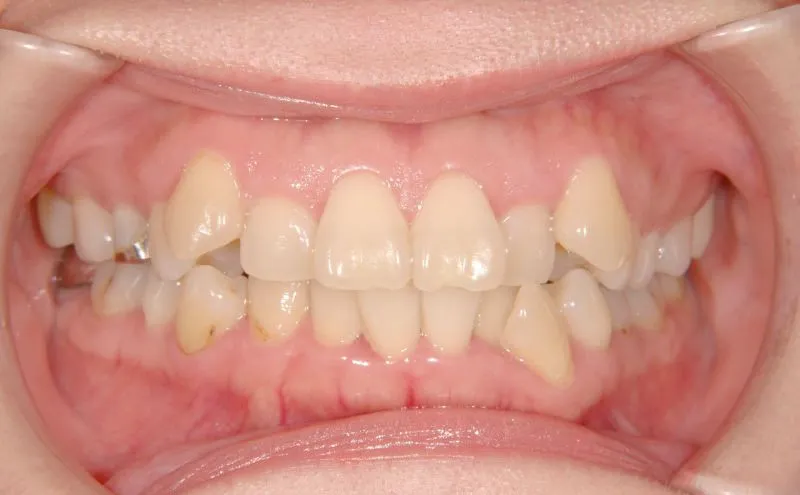

【大人の矯正】ガタガタ・八重歯・非抜歯症例・41歳女性【S.I様】

初診時年齢 40歳以上 (女性) 主訴 上下のがたがた・噛み合わない

診断名 叢生 装置名

状態 ガタガタ・でこぼこに生えている(叢生)

八重歯(叢生)

上下のがたがたと噛み合わない事を主訴に来院されました。

初診